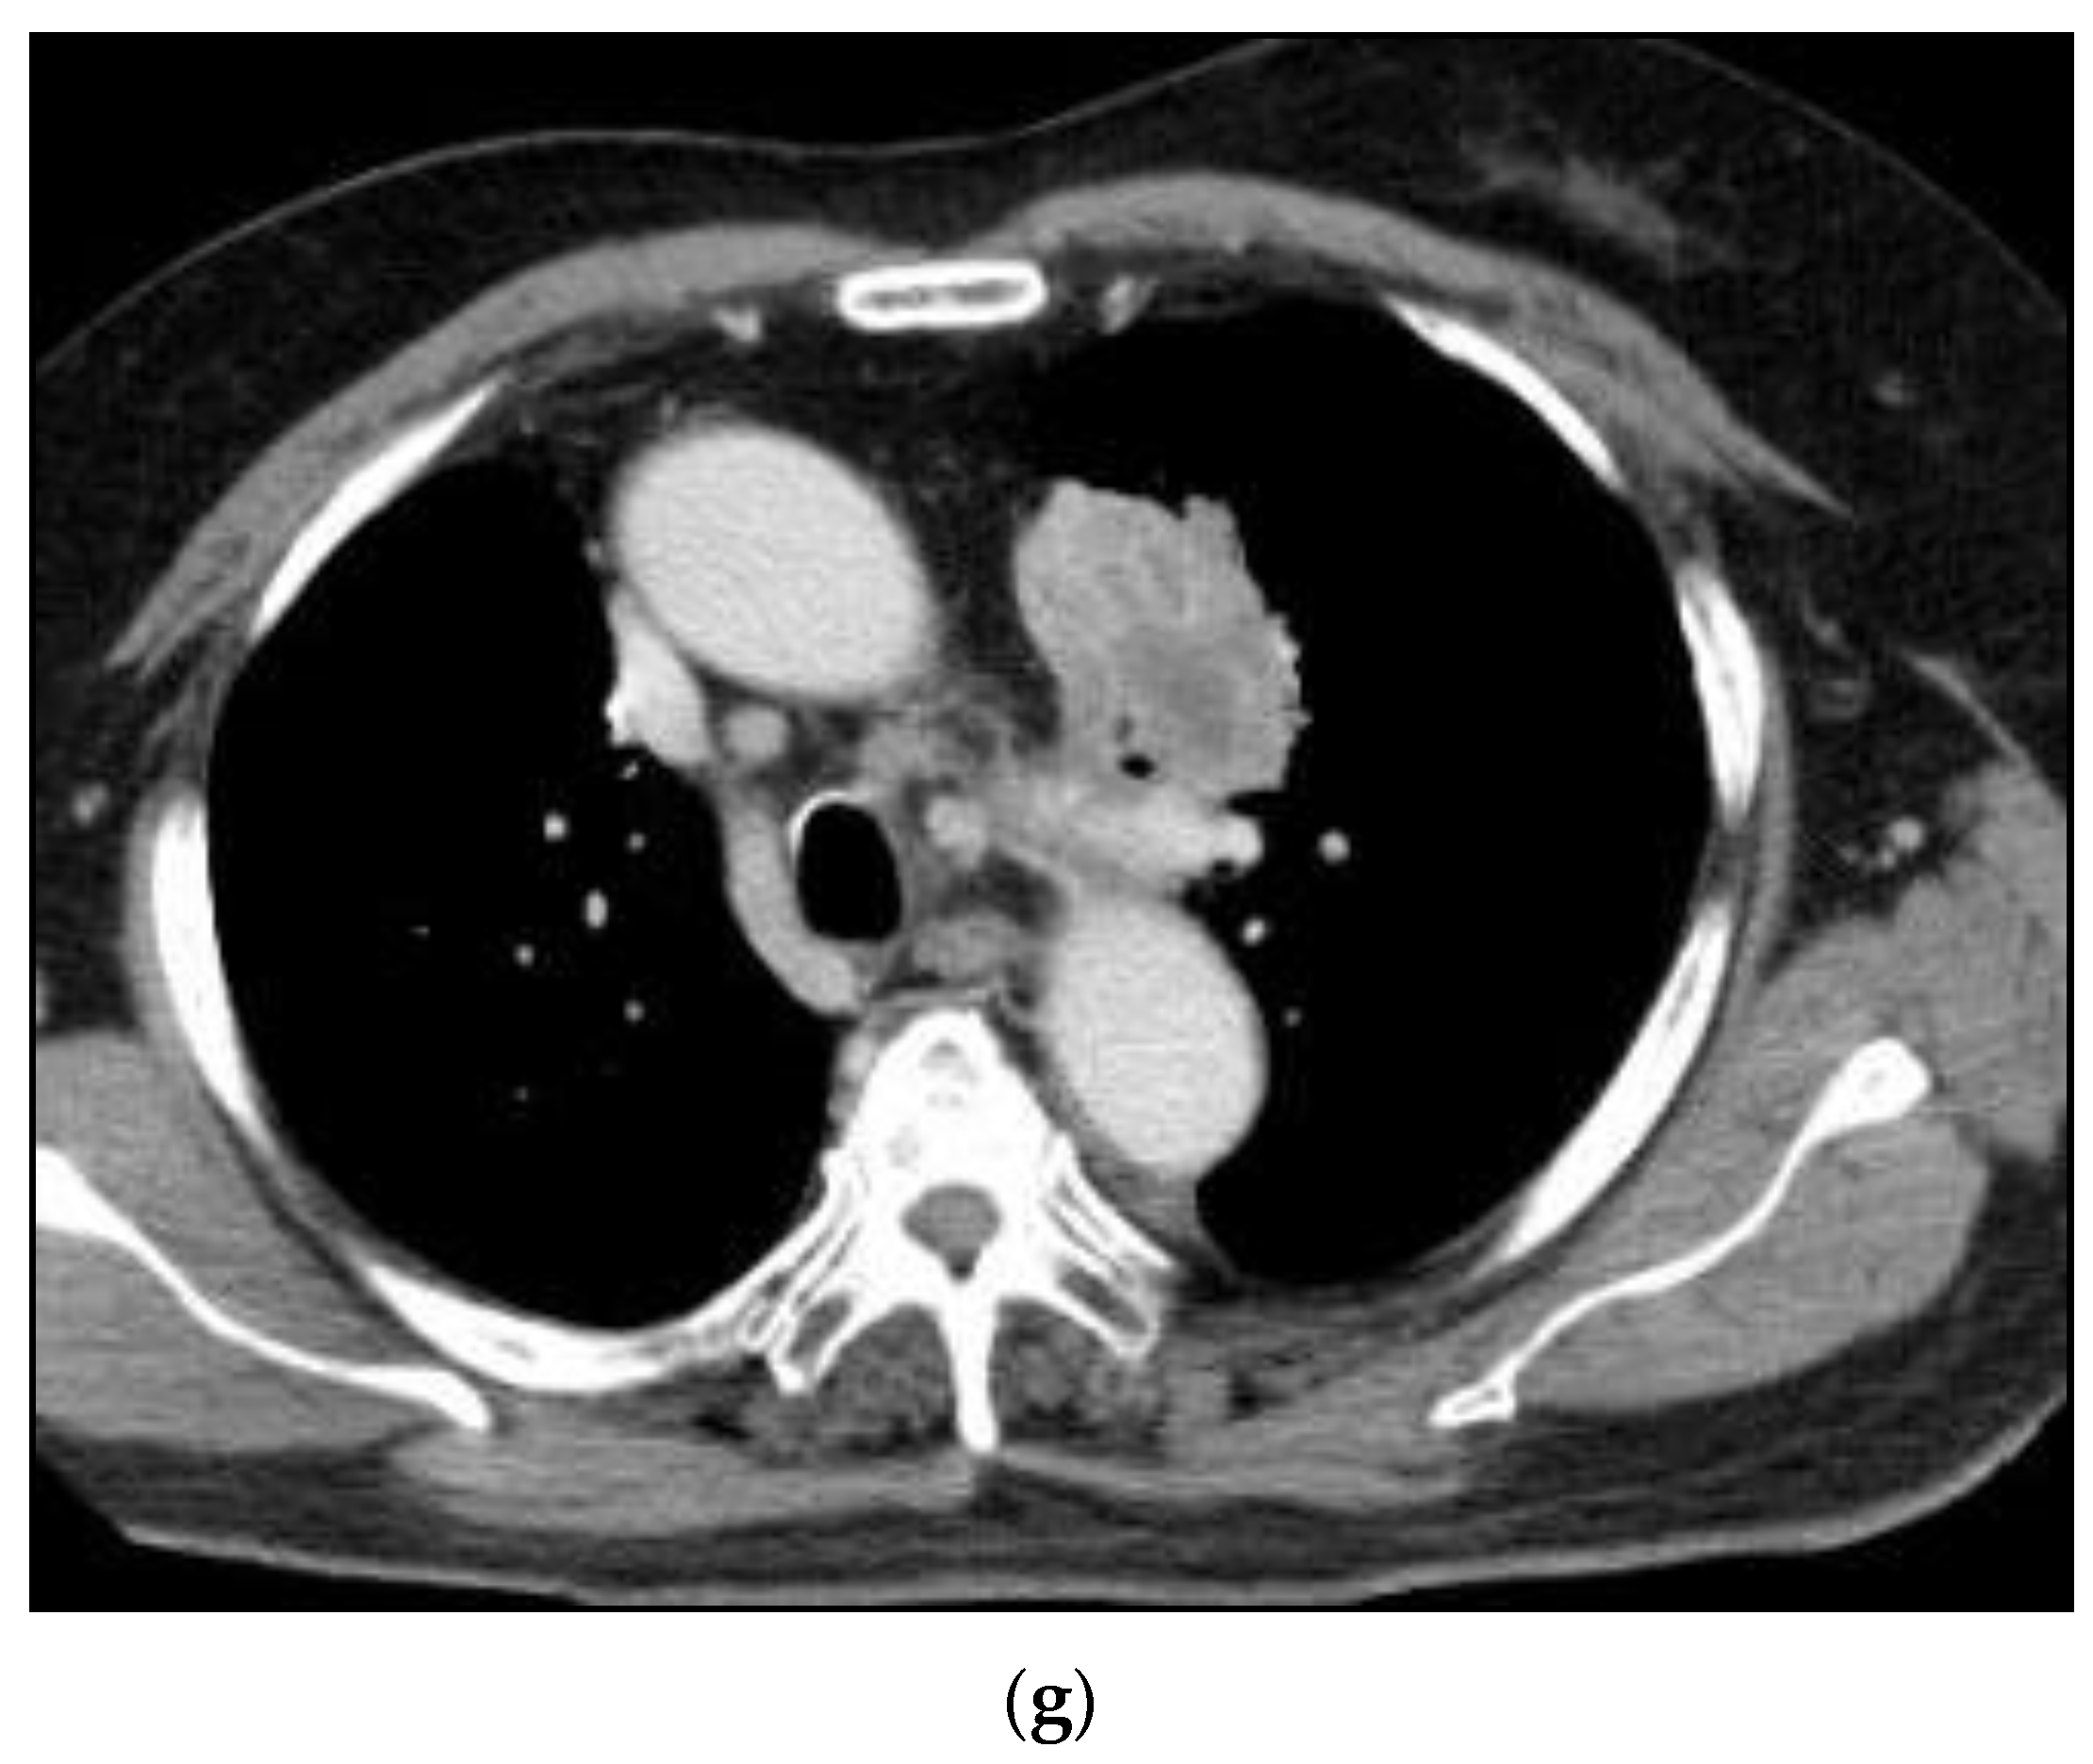

Case 1: A 67-year-old man consulted our clinic with a local recurrence of lung cancer in the left pulmonary hilum (Figure 10). He had got systemic chemotherapy and radiotherapy. Symptoms at consultation were severe cough and respiratory distress. The first treatment through the bronchial arteries was carried out by infusing 5-FU; 250 mg, CDDP; 20 mg, DOC; 20 mg, BV; 200 mg with embolization by 3.0 mg of HepaSphere (50–100 micron). In total, 8 sessions of treatment have been repeated. The patient at present (April 2022) has no clinical symptoms except for a slight cough with no clinical problems in the activity of daily life (ADL).

Figure 10. Recurrent adenocarcinoma in the lung. 67-years-old man. (a): Contrast-enhanced CT A tumor in the left upper lobe invading mediastinum with mediastinal lymph node metastases. The longitudinal diameter was 67 mm. (b): A volume rendering 3D image of the aorta and its’ branches. The main left bronchial artery (arrow) was clearly shown to arise from the anterior wall of the descending aorta. (c): Selective DSA (Digital Subtraction Angiography) of the left main bronchial artery. It was difficult to assess the tumor supply from the bronchial arteriography. (d): Angio-CT of the bronchial artery. The blood supply to the whole tumor was recognized by infusion of contrast into the left bronchial artery. (e): A contrast-enhanced in a month after the initial therapy. Tumor reduction was observed. The diameter was 50 mm. (f): A contrast-enhanced CT in one year after the initial therapy. The diameter was 51 mm. Six sessions of treatment were carried out in one year. (g) A contrast-enhanced CT in 20 months after the initial therapy. The diameter was 56 mm. Eight sessions of treatment were carried out in the clinical course.